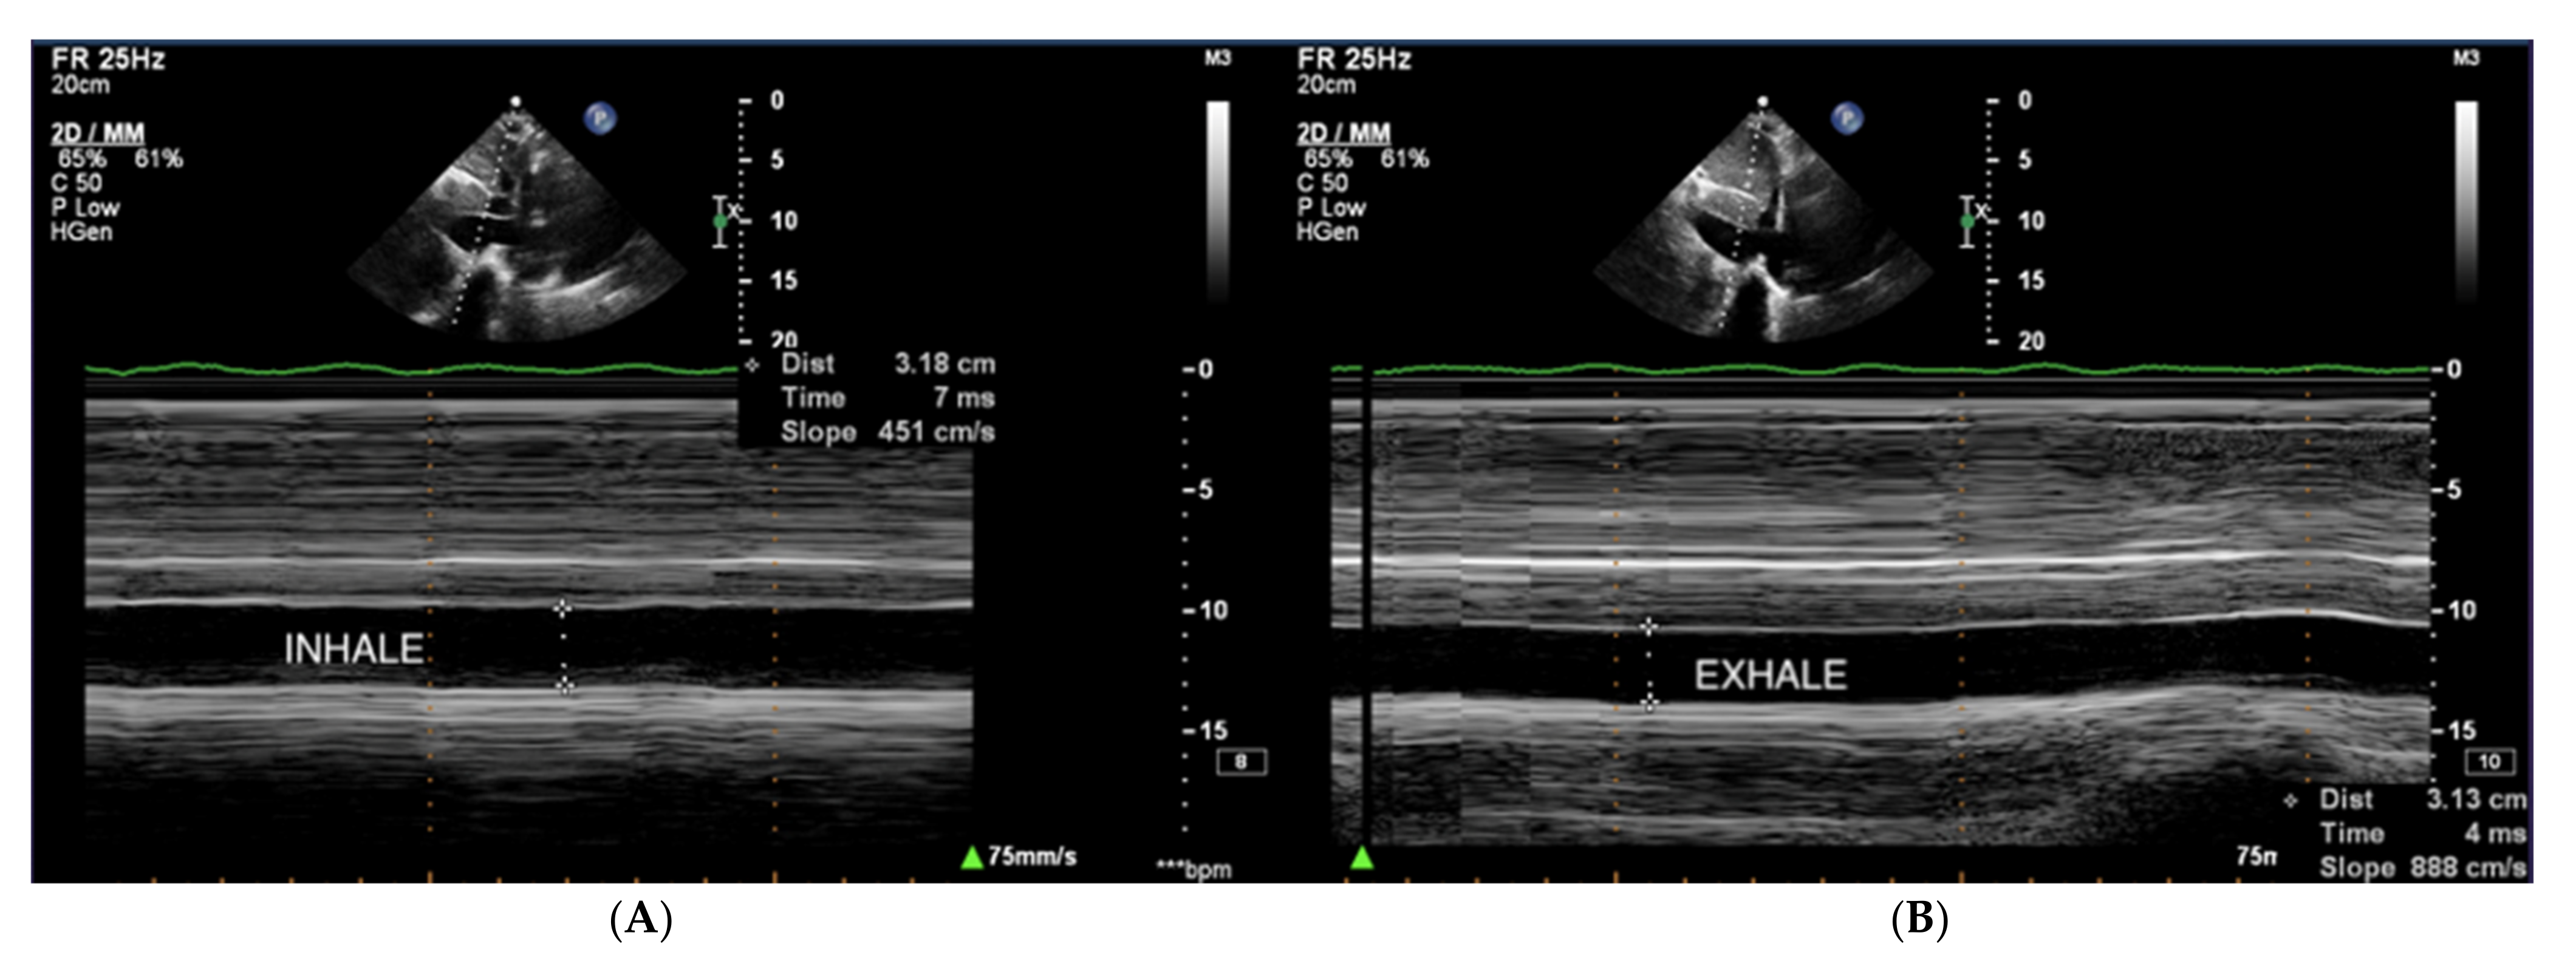

Right atrial pressure (RAP) is usually estimated based on the dimension and collapse rate of the inferior vena cava (IVC) in the subcostal view (Figure 11) [68]. The normal IVC width ranges between 15–21 mm, and IVC collapsibility on inspiration should exceed 50%. Moderately elevated pressure in RA exceeds 5 mmHg, and high pressure exceeds 10 mmHg [69].

Figure 11.

(A,B) IVC, no respiratory variability of IVC in the course of PAH. TTE, subcostal view. IVC: inferior vena cava; TTE: transthoracic echocardiography.

The assessment of the pericardial fluid is of utmost importance in echocardiography in patients with PAH. In a study of 81 patients with PAH, Raymond et al. demonstrated that pericardial effusion was a significant independent predictor of the adverse course of PAH and was associated with higher mortality [25]. Pericardial effusion can be assessed by 2D echocardiography, M mode, and Doppler analysis. However, four views (subcostal, four-chamber, and parasternal long and short axes) are recommended to determine the maximum thickness and precise location of the fluid [26]. Pericardial fluid in impending cardiac tamponade may be associated with the diastolic collapse of the right ventricle and left atrium, significant variability of inflow through the tricuspid valve (an increase of 50%), and mitral valve (a decrease of 25%) on the inhale; and decreased respiratory variation of the inferior vena cava due to increased central venous pressure [27]. However, in patients with advanced pulmonary hypertension, these features may be absent, even in cases where a large volume of pericardial fluid is present.